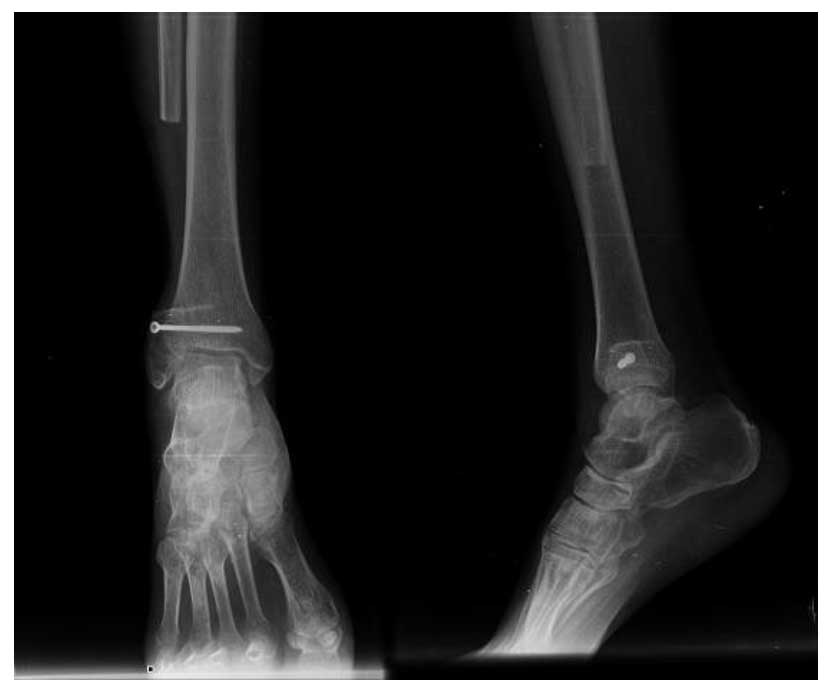

Ameliyat Sonrası: Röntgende distal fibula rezeksiyonu ve ayak bileğinin bir vida ile güçlendirilmesi görülmekte.